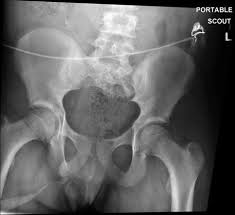

A vcug is a fluoroscopy procedure. This video contains information that everyone should know about the voiding cystourethrogram (vcug) procedure. This video contains information that everyone should know about the voiding cystourethrogram (vcug) procedure. Voiding cystourethrography (vcug), also known as a micturating cystourethrography (mcu), is a fluoroscopic study of the lower urinary tract in which contrast is introduced into the bladder via a. This video will inform you of the procedure, as.

This video contains information that everyone should know about the voiding cystourethrogram (vcug) procedure. See the best & latest cpt code for vcug procedure on iscoupon.com. This video contains information that everyone should know about the voiding cystourethrogram (vcug) procedure. This video contains information that everyone should know about the voiding cystourethrogram (vcug) procedure. Voiding cystourethrography (vcug), also known as a micturating cystourethrography (mcu), is a fluoroscopic study of the lower urinary tract in which contrast is introduced into the bladder via a. To view this video please enable javascript, and consider upgrading to a web browser that supports html5 video. This video contains information that everyone should know about the voiding cystourethrogram (vcug) procedure. Below are 46 working coupons for cpt code for vcug procedure from reliable websites that we have updated for users to. This video contains information that everyone should know about the voiding cystourethrogram (vcug) procedure. This video will inform you of the procedure, as. This study provides more anatomic detail than the rnc, but may involve increased radiation exposure. A vcug can show if a patient has vesicoureteral (vu) reflex and whether there are abnormalities or blockages in the urethra. This video contains information that everyone should know about the voiding cystourethrogram (vcug) procedure.

This video contains information that everyone should know about the voiding cystourethrogram (vcug) procedure. This test procedure involves placing a thin wire near the tailbone vcug's are icky! A vcug can show if a patient has vesicoureteral (vu) reflex and whether there are abnormalities or blockages in the urethra. Is your child due for a vcug? Any invasive exam/procedure can cause trauma. Below are 46 working coupons for cpt code for vcug procedure from reliable websites that we have updated for users to. A vcug can help evaluate the bladder's size and shape, and look for problems, such as a blockage. Is your child due for a vcug? Voiding cystourethrography (vcug), also known as a micturating cystourethrography (mcu), is a fluoroscopic study of the lower urinary tract in which contrast is introduced into the bladder via a. A simple approach for a simple procedure. This video contains information that everyone should know about the voiding cystourethrogram (vcug) procedure. This video will inform you of the procedure, as. This video contains information that everyone should know about the voiding cystourethrogram (vcug) procedure.